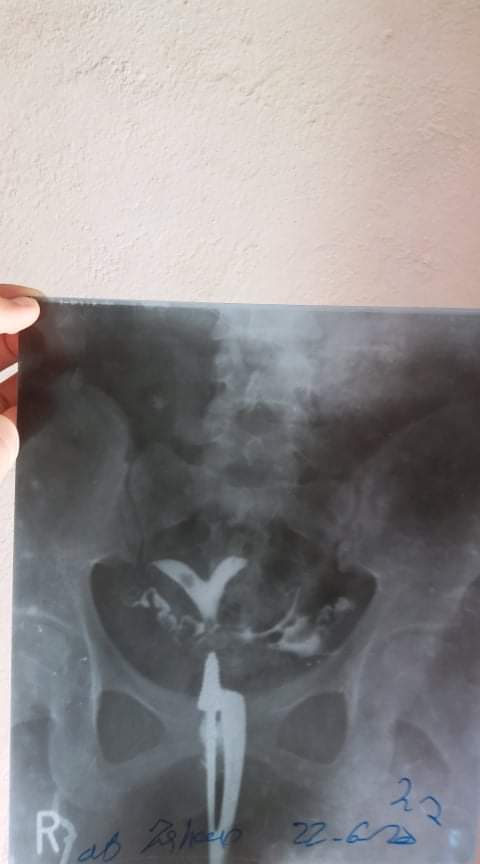

Assalamualaikum We recently had diagnosis doctors says it's because of toxoplasmosis and cmv we have also done HSG x-rays . Doctor says it's problem in it's a bicarnuate uterus. They said surgery is needed. Can bicarnuate uterus be treated without surgery? Is it possible to successfully give birth with a baicarnuat uterus? Is it normal if someone have bicarnuate uterus? Or can effects the baby ?

Respected doctors. It was 40 day .then we visited told it can be the reason of TOXO and CMV and also it can be the reason of bicarnuate uterus. . MMR injection is also given for TOXO and CMV.